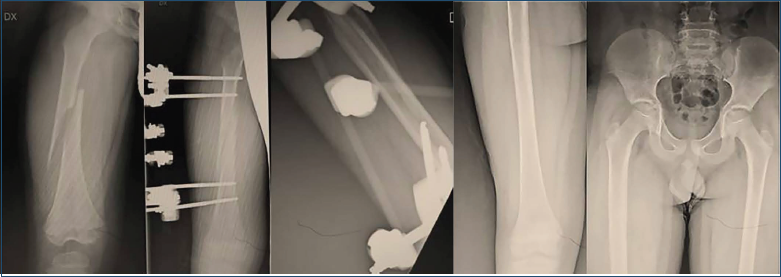

Il fissatore esterno rappresenta di certo una metodica di trattamento delle fratture diafisarie di femore in età pediatrica, specie in presenza di esposizione, danno ai tessuti molli, politrauma o grave comminuzione del focolaio. Difatti il fissatore esterno, come confermato da Lin et al. 24 e da Wang et al. 25, determinerebbe un’osteosintesi più stabile ed un maggiore controllo della rotazione confrontato ai chiodi elastici, maggiore tuttavia il rischio di rigidità legato alla transfissione del tensore della fascia lata. La complicanza maggiormente osservata è infezione dei tramiti, che tuttavia molto raramente può trasformarsi in una vera osteomielite e che sebbene in minor misura, abbiamo osservato anche nei chiodi elastici percutanei dato che usualmente vengono da noi lasciati percutanei. Aslani et al. 26 riportano un alto rischio di rifrattura con incidenza fino al 22% nell’utilizzo del fissatore esterno. Tuttavia nonostante il dato di letteratura, non abbiamo mai osservato tale complicanza. Garner et al.27 descrivono risultati confrontabili a lungo termini in termini di consolidazione, rischio di dismetria, ma un maggiore rischio di mancata consolidazione o ritardo qualora si usassero chiodi elastici in pazienti di peso > 45 kg, per cui in questi consigliamo l’uso del fissatore esterno. I tempi di guarigione sono significativamente più brevi nei chiodi elastici (Fig. 7).

Figura 7. Paziente di anni 8, trauma in motociclo elettrico, concomitava trauma contusivo splenico, trattato in urgenza con fissatore esterno, consolidazione a 90 giorni con follow-up radiologico a 3 anni.